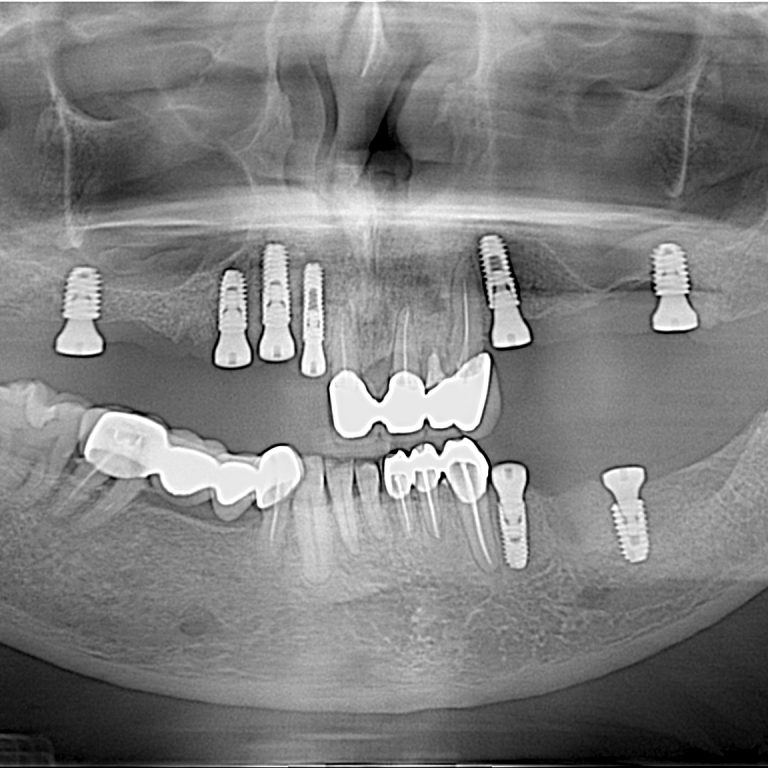

What Is a Dental Implant? A dental implant is a small titanium post that is surgically placed into …

If you have one or more missing teeth, a dental implant is the most reliable and long-lasting solution …

IntroductionDental health is closely linked to our overall well-being. When we lose a tooth, it not only affects …

Dental Implant is the most popular way to replace missing teeth. Placing dental dental implant is pleasant surprise …